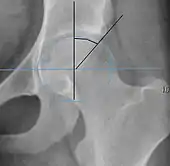

Radiograph of a pincer type impingement.

Projectional radiography ("X-ray")is often considered first line for FAI.[10] Anterior-posterior pelvis and a lateral image of the hip in question should be attained.[10] A 45-degree Dunn view is also recommended.[10][19]

Alpha angle

Measured in 45° Dunn view.

Degree of bulging of the femoral head-neck junction: In normal conditions there is a symmetric concave contour at the junction of the femoral head and neck. Loss of this concavity or bone bulging may lead to cam type impingement. The degree of this deformity can be measured by the alpha angle. Although it can be measured in the cross-lateral view, the 45° Dunn view is considered more sensitive and the frog leg view more specific in determining pathologic values.

• Normal: ≤68° in men, ≤50° in women

• Borderline: 69° to 82° in men, 51° to 56° in women

• Pathological: ≥83° in men and ≥57° in women